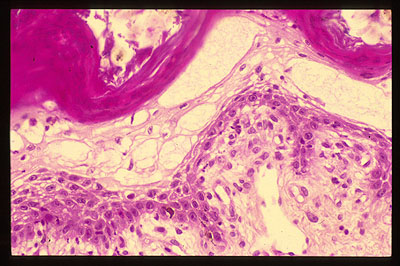

Photo 16 (Hémalun Eosine X 200) : vue rapprochée de la Photo 14

où prédomine la parakératose diffuse de l’épiderme.

Légendes de la Photo 16 :

- Flèche rouge : parakératose épidermique

- Flèches jaune : rares zones de ballonisation des acanthocytes sous-cornés.